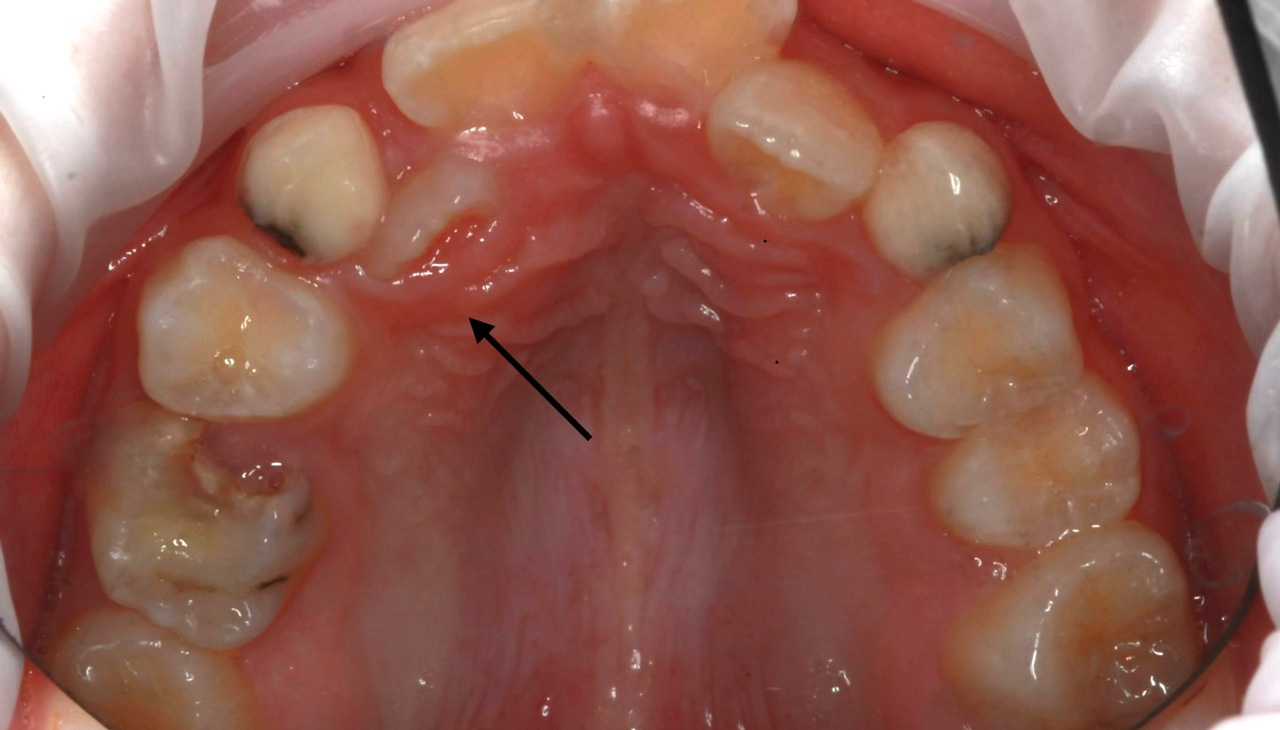

Молочный еще не выпал, а постоянный уже прорезался? Давайте разбираться! (Фото 1)

Коренной просто не помещается в зубном ряду, как следствие, молочный зуб некому растворить. Это может происходить по одной из причин:

- Зачаток постоянного зуба находится в неправильном положении.

- Имеются сверхкомплектные зубы.